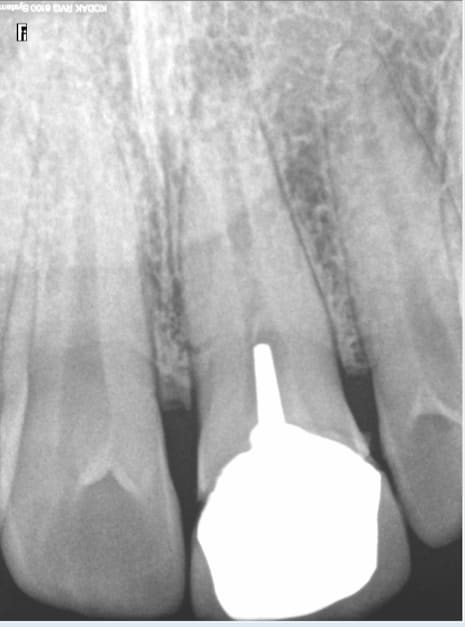

24/01/2016 à 12h18

exemple :

justification : signe d'appel antécédent de choc antérieur.

Doublement pas de bol le garçon pété une incisive qui a été traitée de façon comment dire ? étonnante !

Il est prévenu, il préfère attendre tranquillement sa pèche. A un de ces 4 ! -)))

Je suis sur que tu ne la fais meme pas la radio de l'incisive, me trompe je ? -)

A ma décharge le status n'est pas tout à fait complet il manque quelques apex. -)